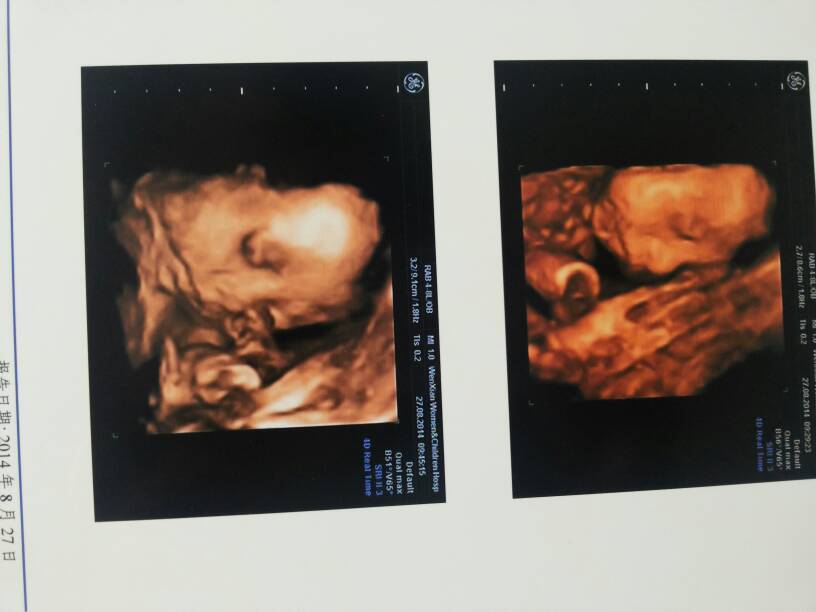

各位有经验的宝妈们帮忙看看男孩女孩?今天四维过了 各位有经验的宝妈们帮忙看看男孩女孩?今天四维过了。 点击展开 王佳贺宝麻@ 2014-08-27 12:45 为您推荐: 其他回答 拍肚子的形状来看看 滴di答da滴di 2014-08-27 13:10 好像男宝哦 风吹 2014-08-27 12:48 你好,根据图片不能判断是男是女而且图片显示宝宝的脸,只能通过B超动态观察胎儿性别。 张笑珠 2014-08-27 12:47 相关问题 今天检查的有经验的宝妈看看男孩女孩?很是好奇! 宝妈们帮忙看看是男孩女孩(⊙o⊙)? 做过四维的宝妈们,帮忙看看正常吗?医生说要下个月再复查,好担心宝宝!